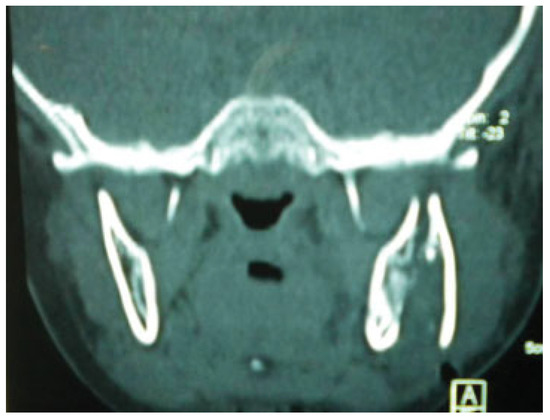

Mandible and Zygomatic Fracture in a 2-Year-Old Patient Due to Dog Bite

Case Report

Procedure